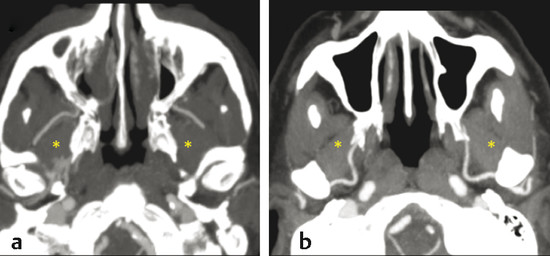

The posterior superior alveolar artery (PSAA) usually represents the first branch of the pterygopalatine segment of the MA. It runs close to the periosteum of the convexity of the maxillary tuberosity and divides into two branches: a lateral descending vessel (dental branch) and an internal vessel (peridental branch). This internal branch perforates the tuberosity of the maxilla and courses endosseously supplying the mucosa of the maxillary sinus and anastomosing with the IOA 2 , 4 , 7 (Fig. 3‑8).